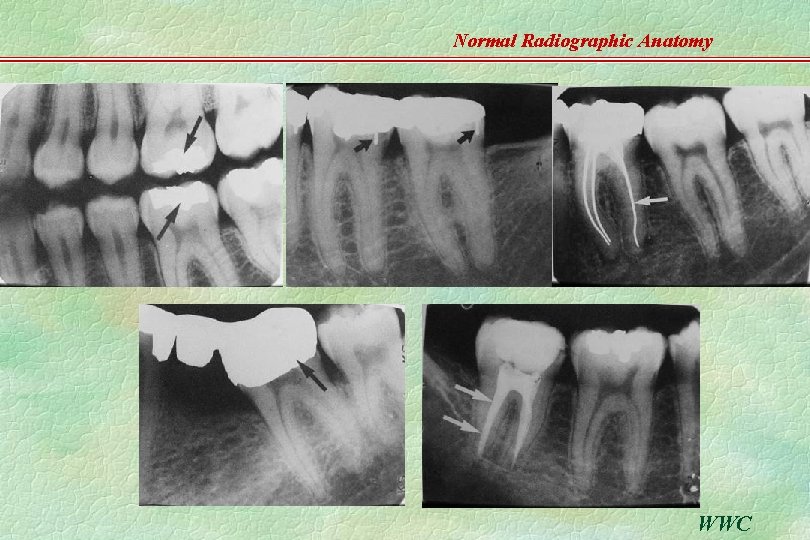

Normal Radiographic Anatomy TEETH u u u Enamel, dentin, cementum, Pulp, root canal Enamelodentin junction C-E junction Normal and developing WWC

Normal Radiographic Anatomy u u Double lamina dura … in root with two eminences (buccal & lingual). Intact apical lamina dura …. a vital pulp. WWC

Normal Radiographic Anatomy Periodontal ligament space u u u R-L (radiolucent) space between root & lamina dura Width of PDL varied by individual, teeth & location; thinner in the middle of the root, slightly widened near the alveolar crest & apex …. fulcrum of physio logical movement of a tooth Double PDL space. . . created by the shape of the tooth. WWC